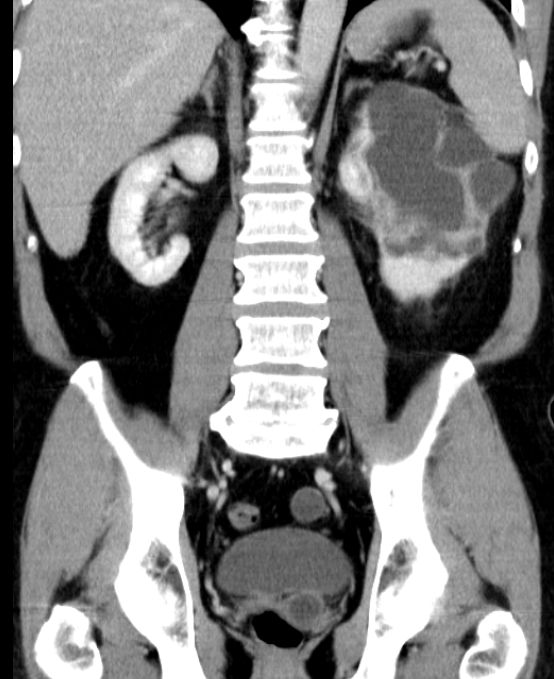

Nierenbecken-Karzinom in einer Doppelniere

Doppelniere links. Im oberen Anteil Hydroureter und Hydropyelons mit Wucherungen eines schlecht differenzierten Urothelkarzinoms mit Plattenepithelmetaplasie, infiltriert das umgebende Fettgewebe.G3. pT3, pN3 (2/3, 1 Lymphknoten mehr als 5 cm) L1. V0. Das CT zeigt den Nierenbeckentumor und eine Lymphknotenmetastase medial des erweiterten Ureters.

Urothelkarzinom der Niere 81-jährige Frau mit einem großen, die linke Niere einnehmendem Tumor. Histologie: Urothelkarzinom.

Die linke Nierenarterie ist von LK-Metastasen eingeschlossen.